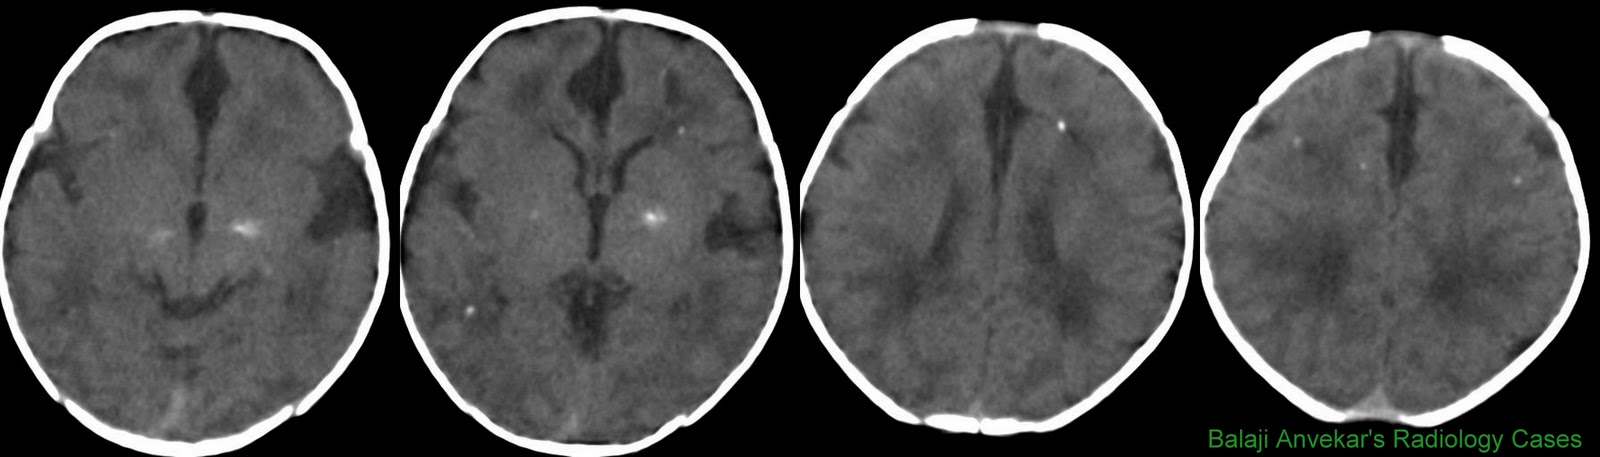

CT Perfusion In Acute Stroke - Boston University

CT Perfusion in Acute Stroke Asim Mian, M.D. Stroke • Infarct: Brain Anatomy •Large Vessels Anterior Circulation - ICAs, MCAs, ACAs. Magnetic Resonance Imaging in Acute Stroke Patients. Stroke. 2002;33:2025-2031. ... Fetch Here